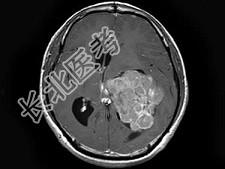

- 单项选择题男,27岁, 一过性黑矇发作半年伴记忆力下降,听觉性失语, 双眼同向性右侧视野缺损,无头痛、呕吐, MRI平扫及增强扫描,最可能的诊断为 ( )

A、侧脑室脑膜瘤

B、侧脑室室管膜瘤

C、侧脑室乳头状瘤

D、侧脑室星形细胞瘤